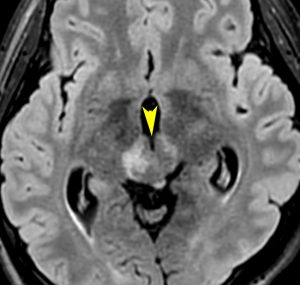

germinomaの視床浸潤:ミッキーマウスの耳

松果体ジャーミノーマは両側視床に浸潤して視床浮腫を生じます。真ん中に第3脳室後半部の割れ目が残っているのが特徴的な所見です。ミッキーマウスの耳みたいになります。かなり特異的な所見であり診断に有用です。右下は治療後です。